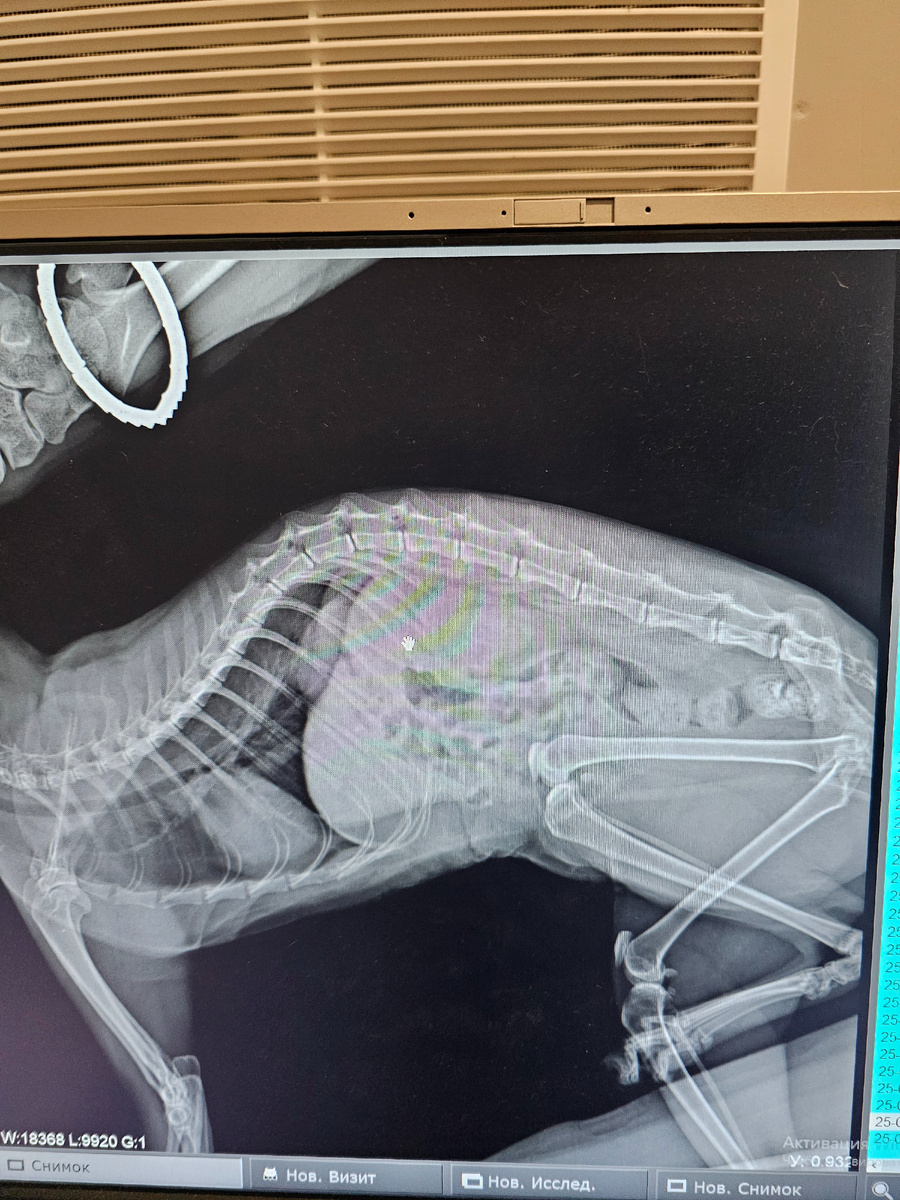

Вчера ездили делали рентген, и он показал опухоль.

Фото автора. Рентген Фасольки.